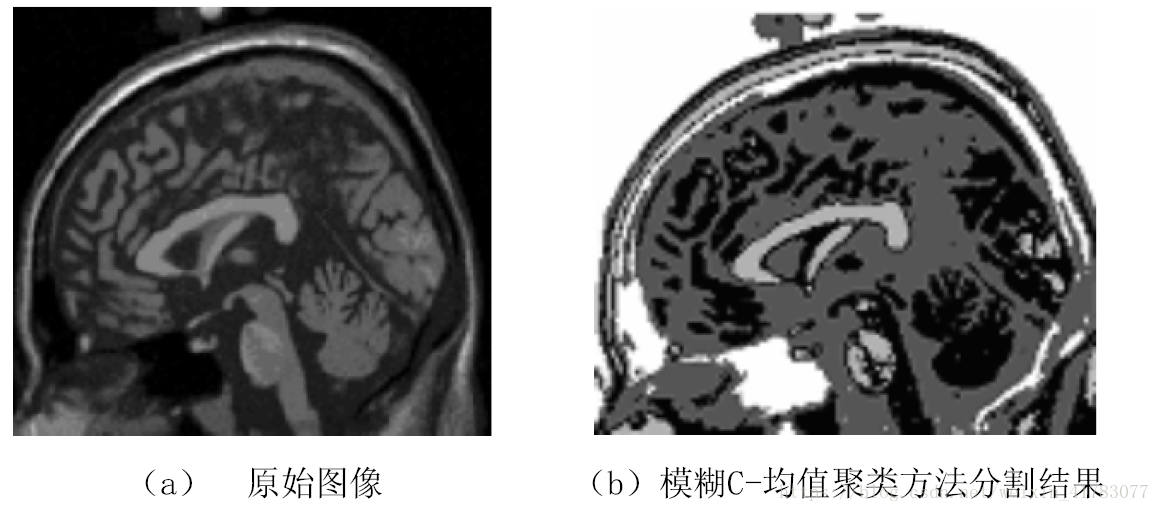

图1为对一幅大脑医学图像应用模糊C-均值聚算法分割的结果,该方法中应用模糊C-均值聚类算法完成了对医学图像的分割,将其分为各具特性的4部分。图5(a)是一幅原始医学图像,图5(b)是分割的结果。

图5 模糊C-均值聚类方法分割大脑医学图像

从图5中可以看出对于图中面积比较大的部分取得了较好的分割结果,但是对于一些面积很小的部分结果不太好。还要进一步研究。